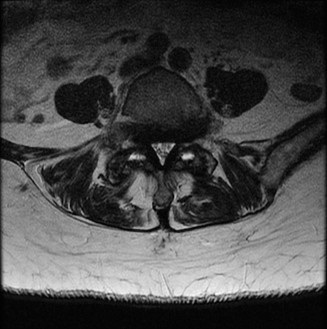

To contextualize the decision-making algorithm, consider the classic presentation of a middle-aged patient with multiple medical comorbidities. A paradigmatic case involves a 48-year-old obese female (Body Mass Index of 43) with poorly controlled diabetes mellitus who presents with severe, unrelenting low back pain, fevers, and chills. Advanced imaging, specifically magnetic resonance imaging (MRI), typically demonstrates discitis involving the L4–5 disc space with adjacent osteomyelitis of the L4 and L5 vertebral bodies. Crucially, in many early or medically responsive cases, there is an absence of epidural abscess formation, and standing radiographs reveal relatively normal sagittal and coronal alignment. When such a patient is neurologically intact—lacking saddle anesthesia, bowel/bladder incontinence, or upper motor neuron signs—the immediate clinical imperative shifts from urgent surgical decompression to aggressive pathogen identification and targeted antimicrobial therapy.

When surgical intervention becomes unavoidable, meticulous pre-operative planning is the cornerstone of a successful outcome. Advanced imaging is non-negotiable. An MRI with and without gadolinium contrast is the gold standard for defining the extent of the epidural abscess, the degree of neural compression, and the involvement of adjacent paraspinal musculature (e.g., psoas abscess). T1-weighted images typically show hypointense signals in the infected marrow, while T2-weighted and STIR sequences reveal hyperintense fluid and edema in the disc space and vertebral bodies. Gadolinium enhancement highlights the vascularized inflammatory phlegmon and the capsule of any abscesses.

Once instrumentation is placed, a wide laminectomy is performed at the affected level. The ligamentum flavum is excised, exposing the thecal sac and traversing nerve roots. If an epidural abscess is present, it is meticulously evacuated using gentle suction and blunt dissectors. The nerve roots are then mobilized medially to access the infected disc space via a transforaminal approach.